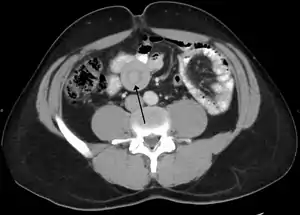

An intussusception is often suspected based on history and physical exam, including observation of Dance's sign. A digital rectal examination is particularly helpful in children, as part of the intussusceptum may be felt by the finger. A definite diagnosis often requires confirmation by diagnostic imaging modalities. Ultrasound is the imaging modality of choice for diagnosis and exclusion of intussusception, due to its high accuracy and lack of radiation. The appearance of target sign (also called "doughnut sign" on a sonograph, usually around 3 cm in diameter, confirms the diagnosis. The image seen on transverse sonography or computed tomography is that of a doughnut shape, created by the hyperechoic central core of bowel and mesentery surrounded by the hypoechoic outer edematous bowel.[10] In longitudinal imaging, intussusception resembles a sandwich.[10] It is also called "pseudokidney" sign because hyperechoic tubular centre is covered by a hypoechoic rim producing a kidney-like appearance.[11]

In adults, intussusception represents the cause of approximately 1% of bowel obstructions and is frequently associated with neoplasm, malignant or otherwise.[16]